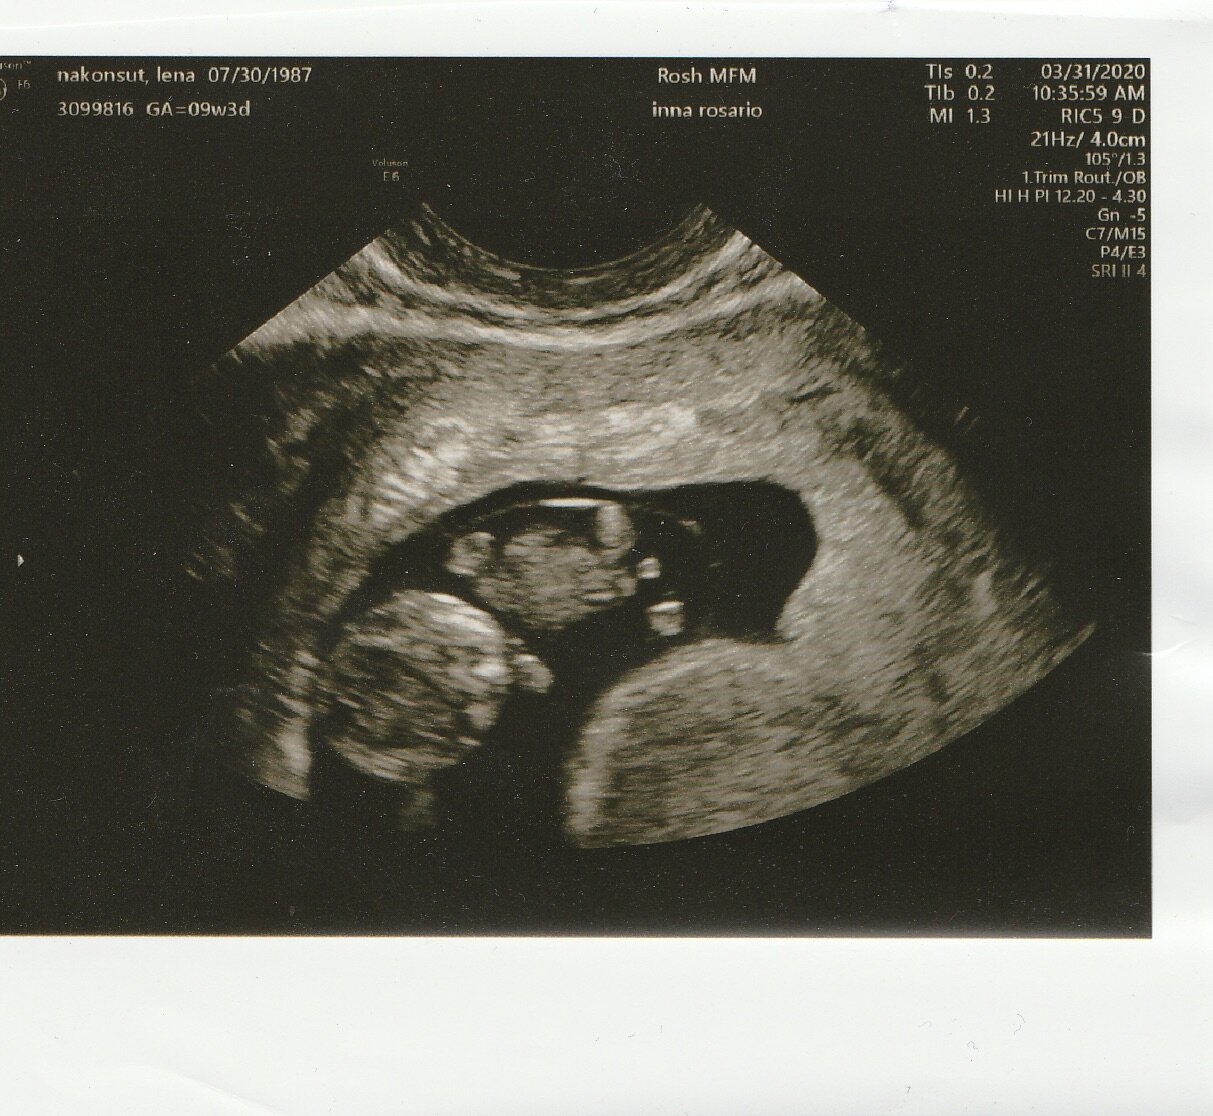

Baby Hunter

We’re having a boy!

Some say pregnancy is the worst. Some say it’s the best.

It is what it is. But we got through with a lot of TV shows, delivery, online shopping, and motivational speeches. We can’t overstate how crazy of a year it’s been in so many ways. But if it means bringing Hunter into this world, it was worth it to us. Here are some highlights: